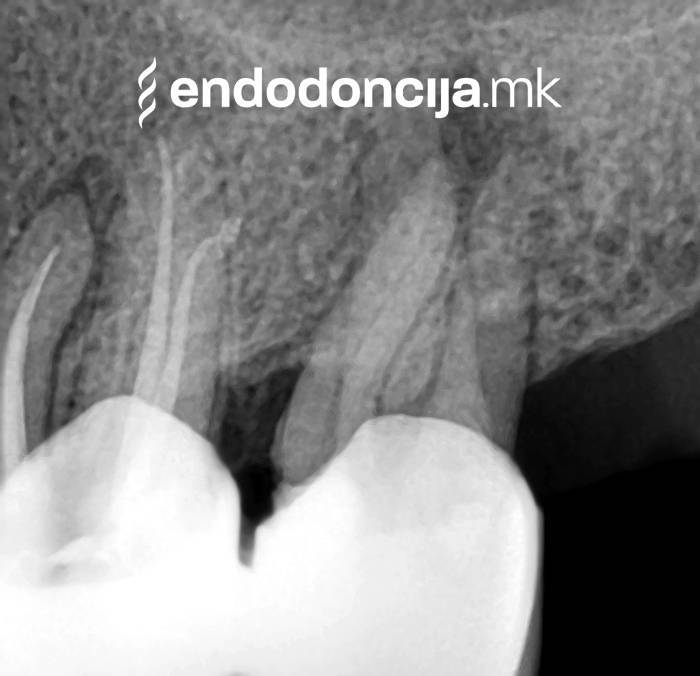

Κατά τη διάρκεια της επεξεργασίας του ριζικού σωλήνα, τα λεπτά όργανα ενδέχεται να σπάσουν. Αυτό μπορεί να αποτελέσει εμπόδιο για την πλήρη προετοιμασία και τον καθαρισμό του ριζικού σωλήνα. Με μια μικροσκοπική επεξεργασία του ριζικού σωλήνα μπορεί να είναι δυνατή η απομάκρυνσή τους υπό ορισμένες συνθήκες, χωρίς να καταστρέφεται η ουσία των δοντιών.

Κατά τη διάρκεια προηγούμενων θεραπειών, το δόντι μπορεί όχι μόνο να έχει αποδυναμωθεί από τη μηχανική επεξεργασία του ριζικού σωλήνα αλλά και από τη στερέωση και την αγκύρωση ενός ρίζα. Όταν αναθεωρείται η επεξεργασία ενός ριζικού καναλιού, αυτοί οι πείροι πρέπει να αφαιρούνται όσο το δυνατόν πιο προσεκτικά για να διατηρούν σημαντική ουσία των δοντιών.